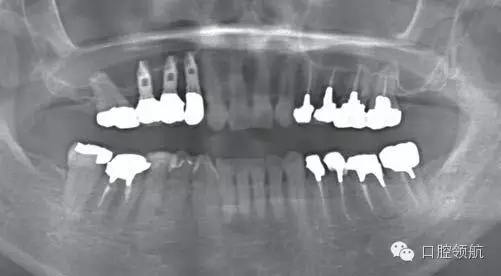

(左上第四顆牙)拔牙后即刻種植,(左上第五、六顆牙)位置用β-TCP做上頜竇內(nèi)提升同期植入種植體的病例(圖1)。

圖1 術(shù)前的曲面斷層影像